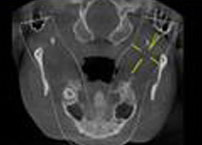

除常规检查之外,想要全面了解患者口腔情况,还必须依靠被喻为种植医生第三只眼并开创微创可视种植新时代的全口CT,借助外科导板三维立体为患者制定较好的种植方案。